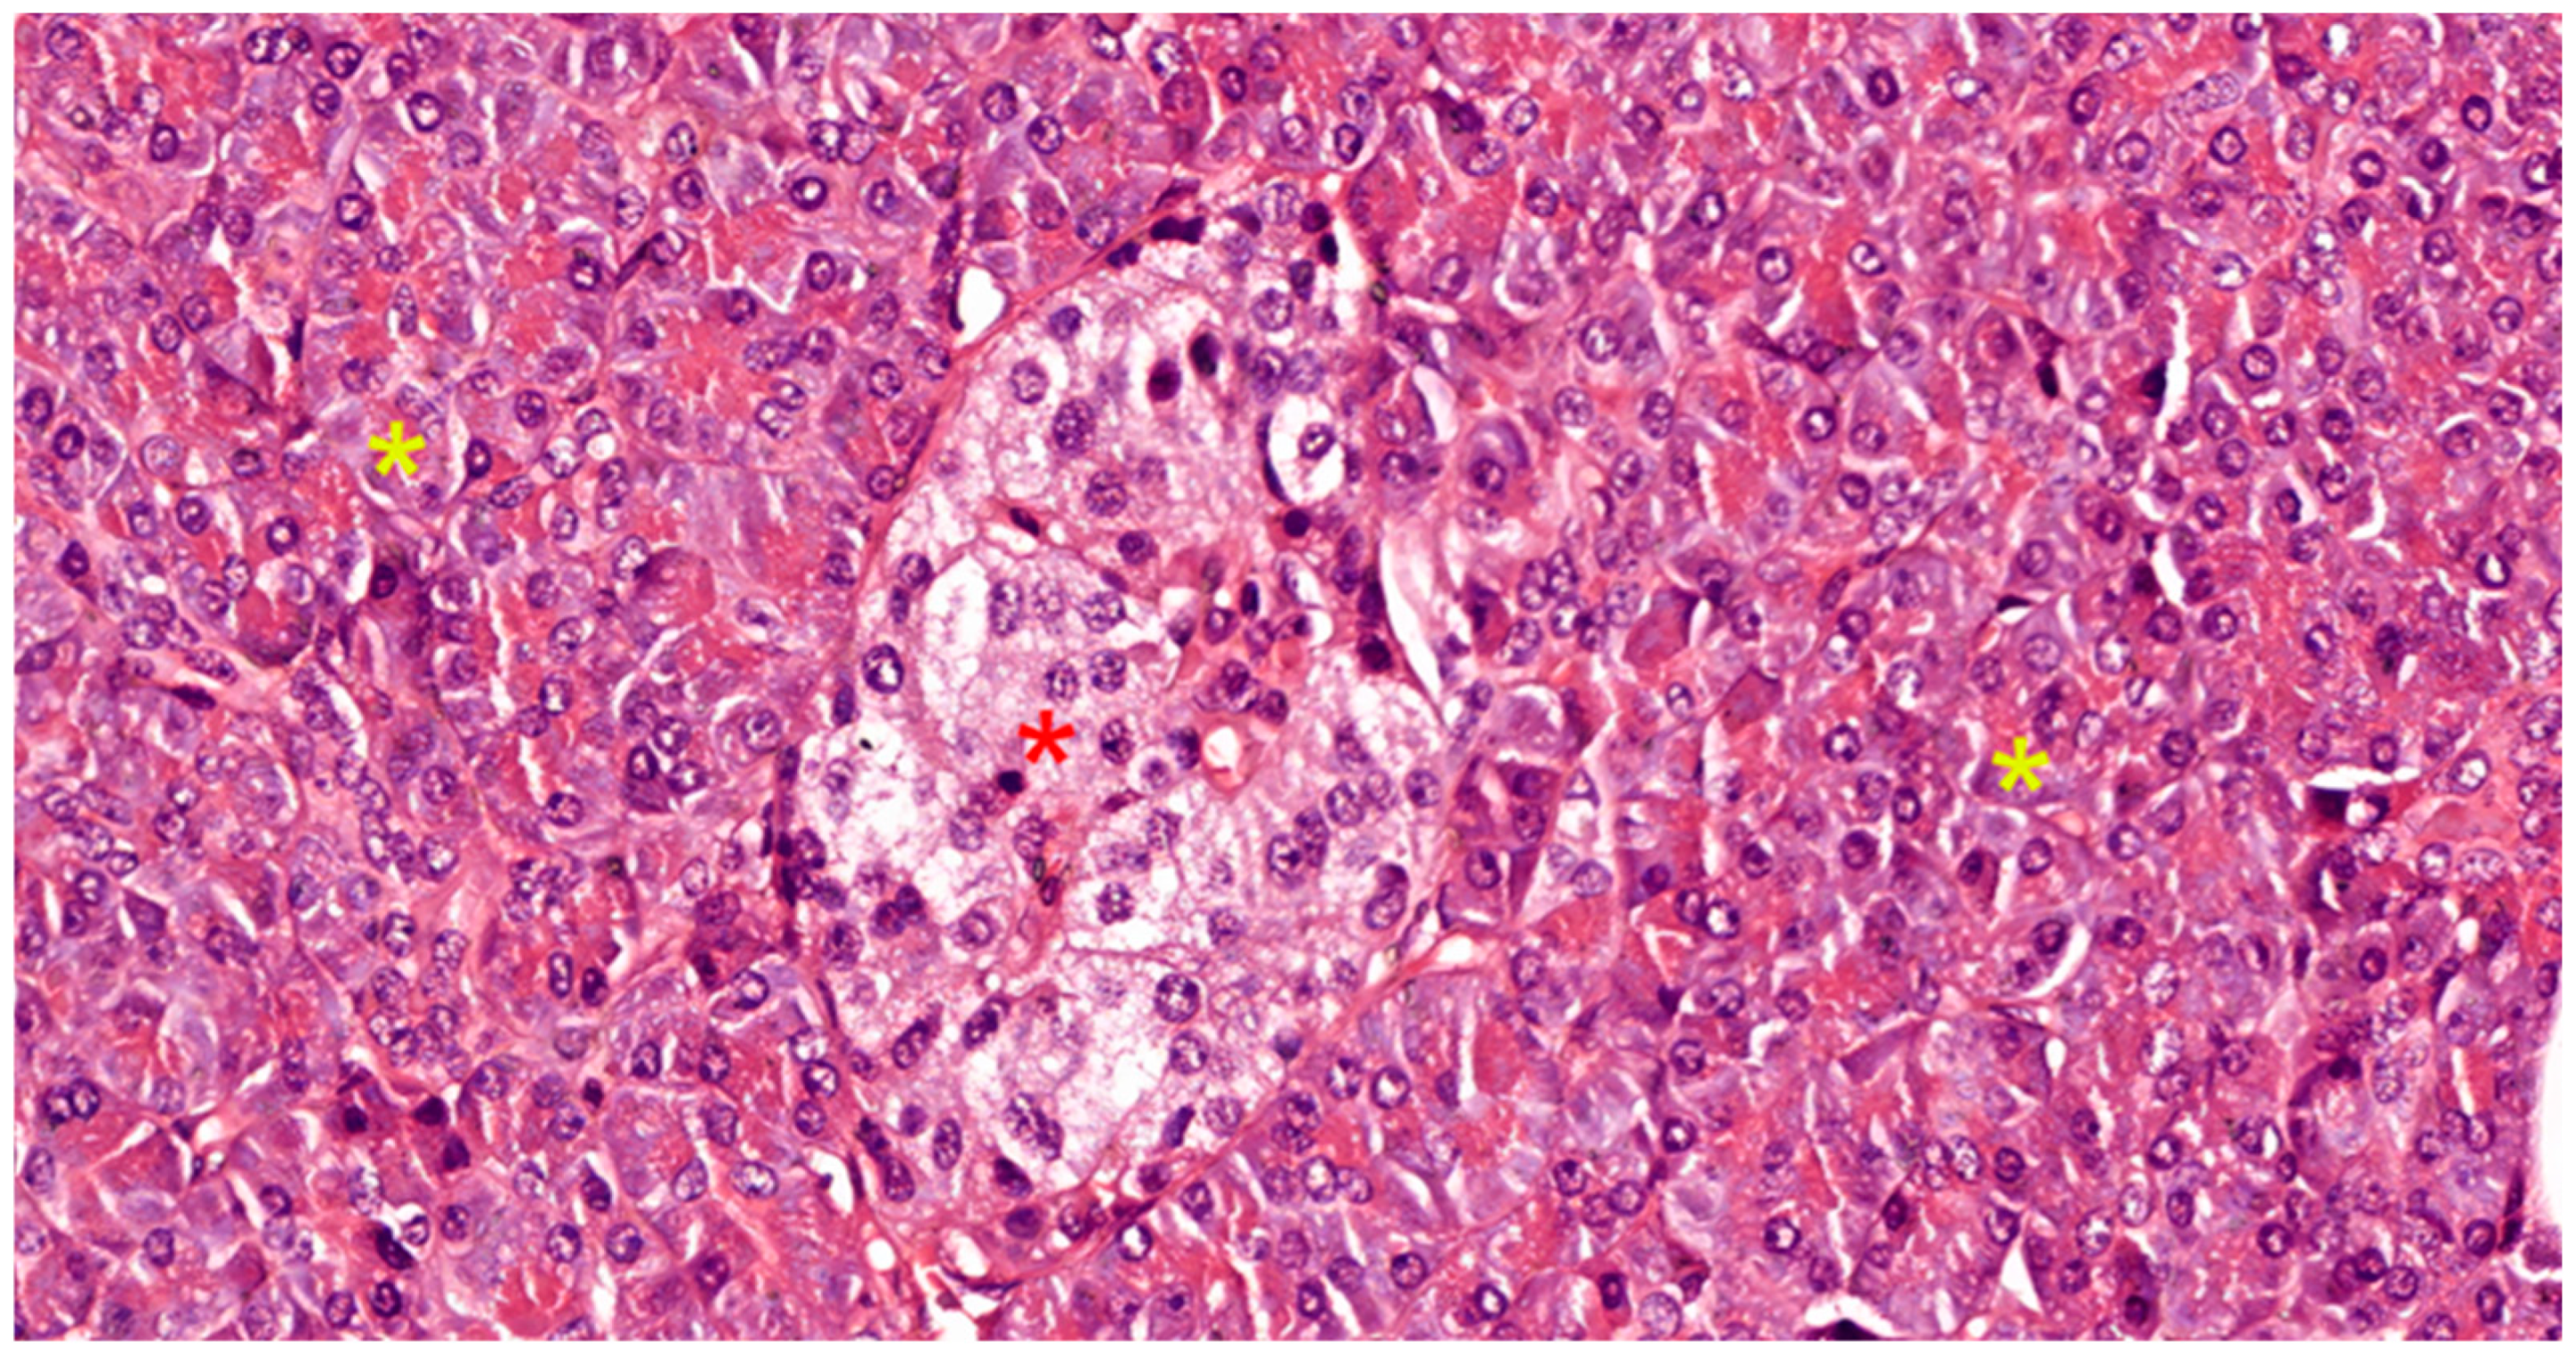

- Centro-acinar cells—delimiting the lumen together with acinar cells; they are small, flattened, or cuboidal in shape; the cytoplasm is pale, and the nucleus is oval; these cells are considered reserve cells for acinar and ductal cells (see Figure 4a).

- Intralobular ducts—represented by intercalated ducts that continue the lumen of the acini and are delimited by simple cuboidal epithelium; intercalated ducts fuse to form proper intralobular ducts, which are larger and delimited by simple cuboidal or columnar epithelium; around these ducts, a loose connective stroma can be observed, with numerous reticulin fibers, yet quantitatively reduced overall; unlike major salivary glands, the exocrine pancreas does not have striated ducts (see Figure 4a,b).

- Interlobular ducts—located in connective trabeculae; they have a wide lumen and are delimited by simple columnar epithelium; they are surrounded by well-represented, dense, irregular connective tissue, which contains fibroblasts and myofibroblasts (see Figure 5).